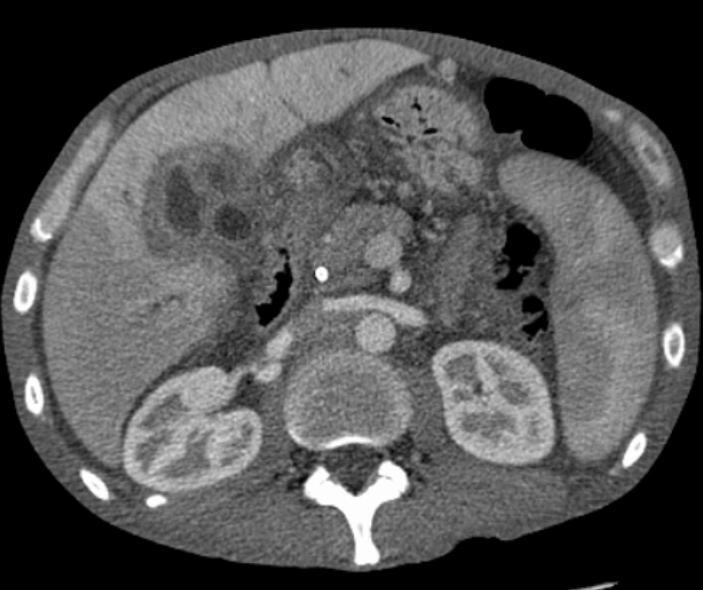

5. 2. 복부 영상

간 및 담도 초음파는 폐쇄성 황달이 의심되는 환자의 초기 영상 검사로 자주 사용된다.[157][158] 초음파는 폐쇄와 담관 확장을 확인할 수 있으며, 경우에 따라 담관암을 진단하는 데 충분할 수 있다.[159] 컴퓨터 단층촬영(CT) 스캔도 담관암 진단에 중요한 역할을 할 수 있다.[160][161][162]